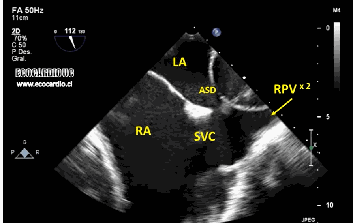

Transözofageal Ekokardiyografi

Bazı durumlarda ise kalbi daha net görmek gerekebilir. Özellikle kalp kapakçıklarının detaylı incelenmesi, kalp içinde pıhtı araştırılması veya enfeksiyon şüphesinde transözofageal ekokardiyografi (TEE) yapılır. Bu yöntemde ince bir ultrason probu, yemek borusu yoluyla kalbe yakın bir noktaya yerleştirilir. Çünkü yemek borusu kalbin hemen arkasından geçtiği için görüntüler çok daha net elde edilir.

TEE işlemi sırasında hasta genellikle hafif sakinleştirici alır, böylece rahatsızlık minimum olur. Boyun ve yemek borusu yapıları nedeniyle çok nadir komplikasyonlar olabilir ama genel olarak güvenlidir.